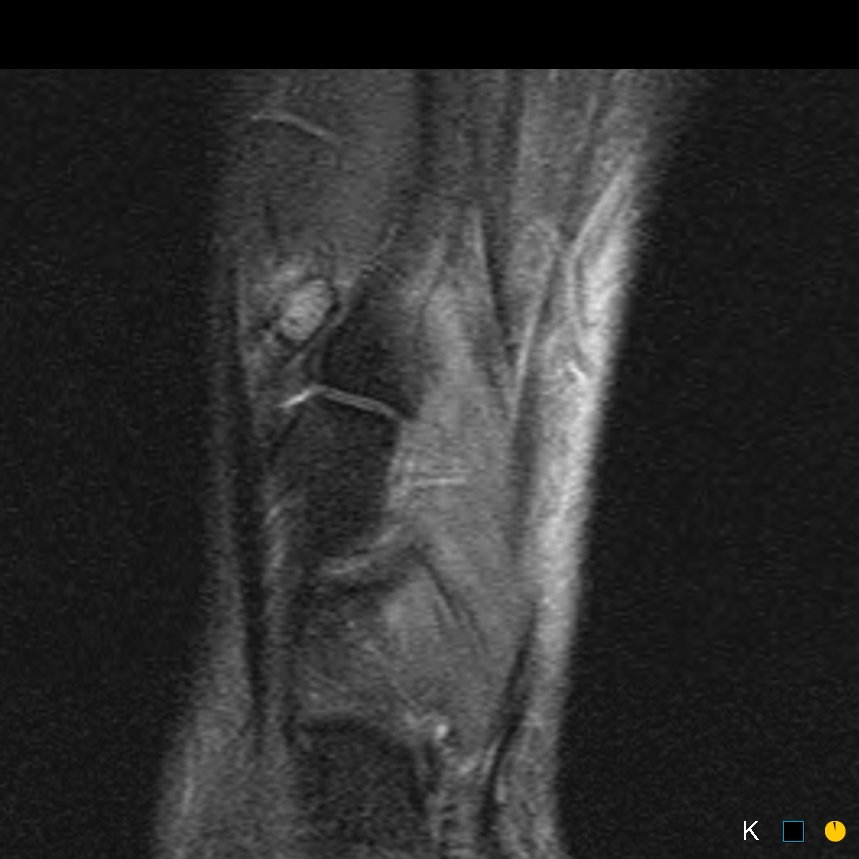

Sprinter. Dorsal midfoot pain

Symptomatic os intermetatarseum

Rx: shoewear adjustment, steroid inj, excision

This case underwent excision, with resolution of symptoms